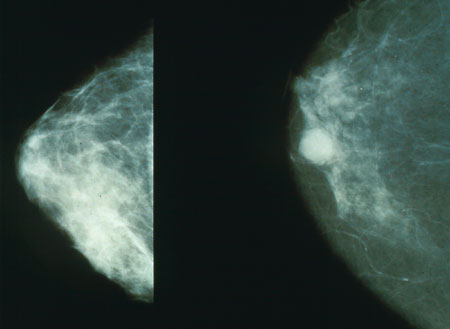

The New York Times, one of whose hobbyhorses is overtesting for and overtreatment of women’s breast issues, has decorated the front page with the latest report on DCIS (ductal carcinoma in situ, a poorly named condition that may or may not be a breast cancer precursor). Some 60,000 women a year are diagnosed with this vaguely understood malady (if malady it is), and most are treated with lumpectomy plus unpleasant chemicals plus unpleasant radiation or with mastectomy, with or without the added unpleasantries. Many of us, myself among them, opt for double mastectomy, just to end the torture.

And the Times reports that all the frenetic treatment does just about nothing to change the outcome: that women with DCIS are no more likely to die of breast cancer than the ordinary woman on the street, a member of the “general population.” Those who do die — an extremely small percentage — “die despite treatment, not for lack of it.”

Yes. Well, this is not exactly news. The study, published yesterday in JAMA Oncology, essentially confirms what we already know: the widespread hysteria over breast cancer and the frantic push to screen every woman on the planet with mammography lead to widespread unnecessary treatment and mutiliation, accomplishing rather little.

Possibly as many as 80% of DCIS occurrences may never evolve into invasive cancers. Estimates range from as few as 20% of cases to as many as 50% of cases turn into cancer. We do not know the correct figures, but we do know that some proportion of DCIS does morph into invasive malignancy.

During the 1980s, before the mammography enthusiasm, women found to have DCIS numbered in the hundreds. Today, 60,000 women are treated for it every year. And there has been no change in the rates of true cancers.